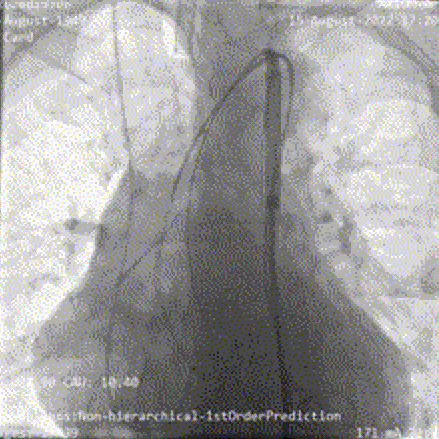

主动脉根部造影提示主动脉瓣重度反流,顺利完成跨瓣操作后予以23mm球囊充分预扩,提示无明显腰征,无造影剂渗漏,冠脉显影正常;

主动脉根部造影

球囊预扩